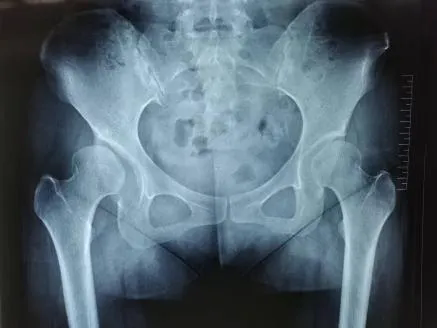

圖1-2:術(shù)前查體

圖3-4:術(shù)前影像(右側(cè)髖關(guān)節(jié)發(fā)育不良)